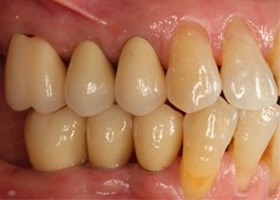

術前缺牙無法咀嚼

治療後全口X光片、口內照片